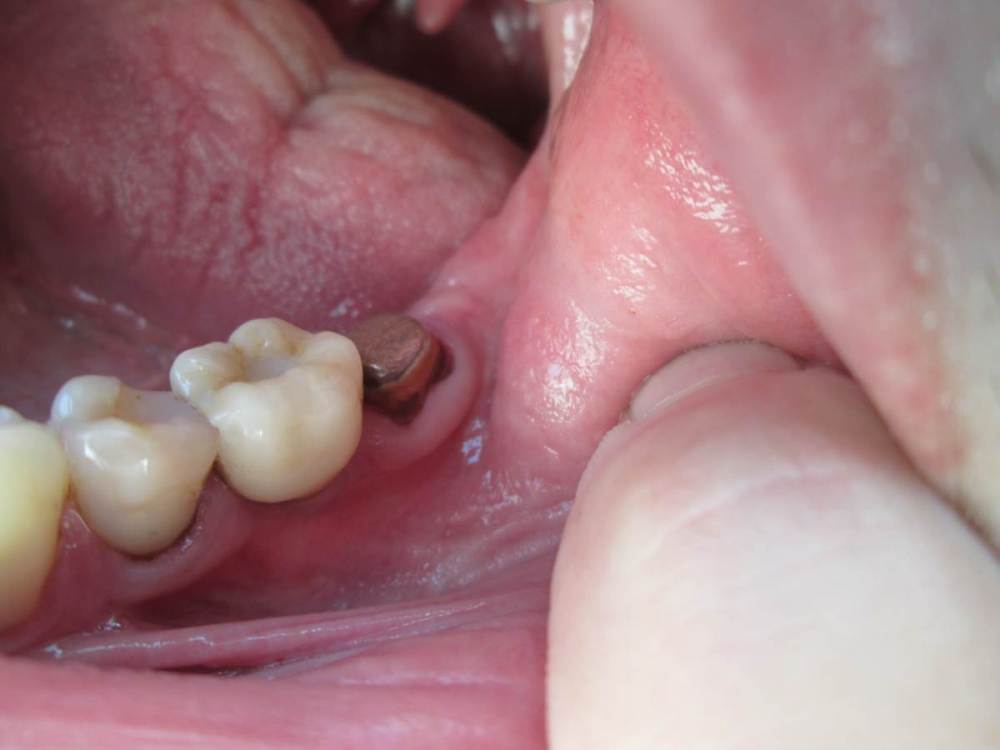

Jonik Опубликовано 29 июня, 2022 Поделиться Опубликовано 29 июня, 2022 Здравствуйте! Поставили коронку на временный цемент, недавно она отвалилась, нужно идти фиксировать на постоянный цемент но коронка мне не совсем нравится. Слой керамики в некоторых местах выходит за пределы металлического основания. Где то слой керамики заглажен к металлу, а где то имеет утолщение. Можно ли фиксировать такую коронку или переделывать. Если поставить эту коронку, могут ли потом возникнуть проблемы с гигиеной или с десной? Ссылка на комментарий

Jonik Опубликовано 30 июня, 2022 Автор Поделиться Опубликовано 30 июня, 2022 31 минуту назад, Doc сказал: Тут весь вопрос в том, что это было. Если керамическое плечо, то это нормально и даже когда-то приветствовалось. Если же техник просто металл не дотянул, а потом решил керамикой доляпать, то это совсем другой вопрос. Как во рту сидит? По десне все хорошо, либо над, либо глубоко под? Где уступ? Коронка точно без плеча. Когда была первая примерка врач отправил коронку на корректировку, сказал что нужно поправить немного. Может как раз это и был недотянутый метал. Как во рту сидит мне не нравится, местами под десну заходит. Ближе к уступу коронка кажется массивной, имеет утолщение возле десны, как бы наплывает на десну, приходится промывать ирригатором. Ссылка на комментарий